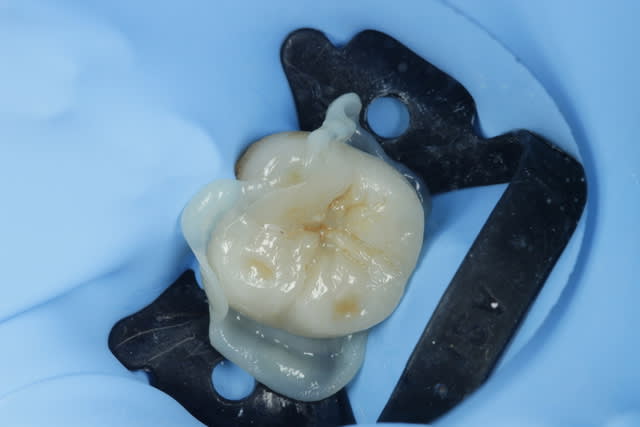

j'ai collé ...

Si le prothésiste avait pu simuler au milieu de cet onlay un petit amalgame avec des bords vieillissant, le mimétisme aurait été parfait...

Toute blague mise à part, très joli onlay, aussi bien la morphologie que les joints quasi invisibles... Je vais faire quelques prières pour que la dent ne se nécrose pas rapidement!

En gros c'est une couronne 9/10ème !